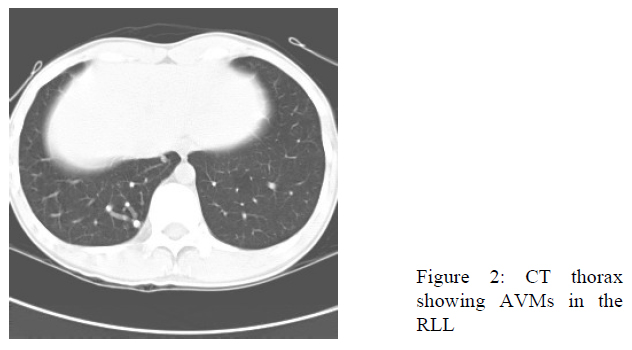

CT thorax was performed subsequently. Four arteriovenous malformations (AVMs) ranged from 0.6cm to 1.5cm were detected in right lower lobe (Fig.2). They all received single artery supply from branches of right lower lobe pulmonary artery and drained to a single vein towards right inferior pulmonary veins. This patient had no telangiectasia over face, chest and upper extremities. There was no mucosal telangiectasia. He had no epistaxis or history of gastrointestinal bleeding. He had no family history of hereditary haemorrhagic telangiectasia (HHT).